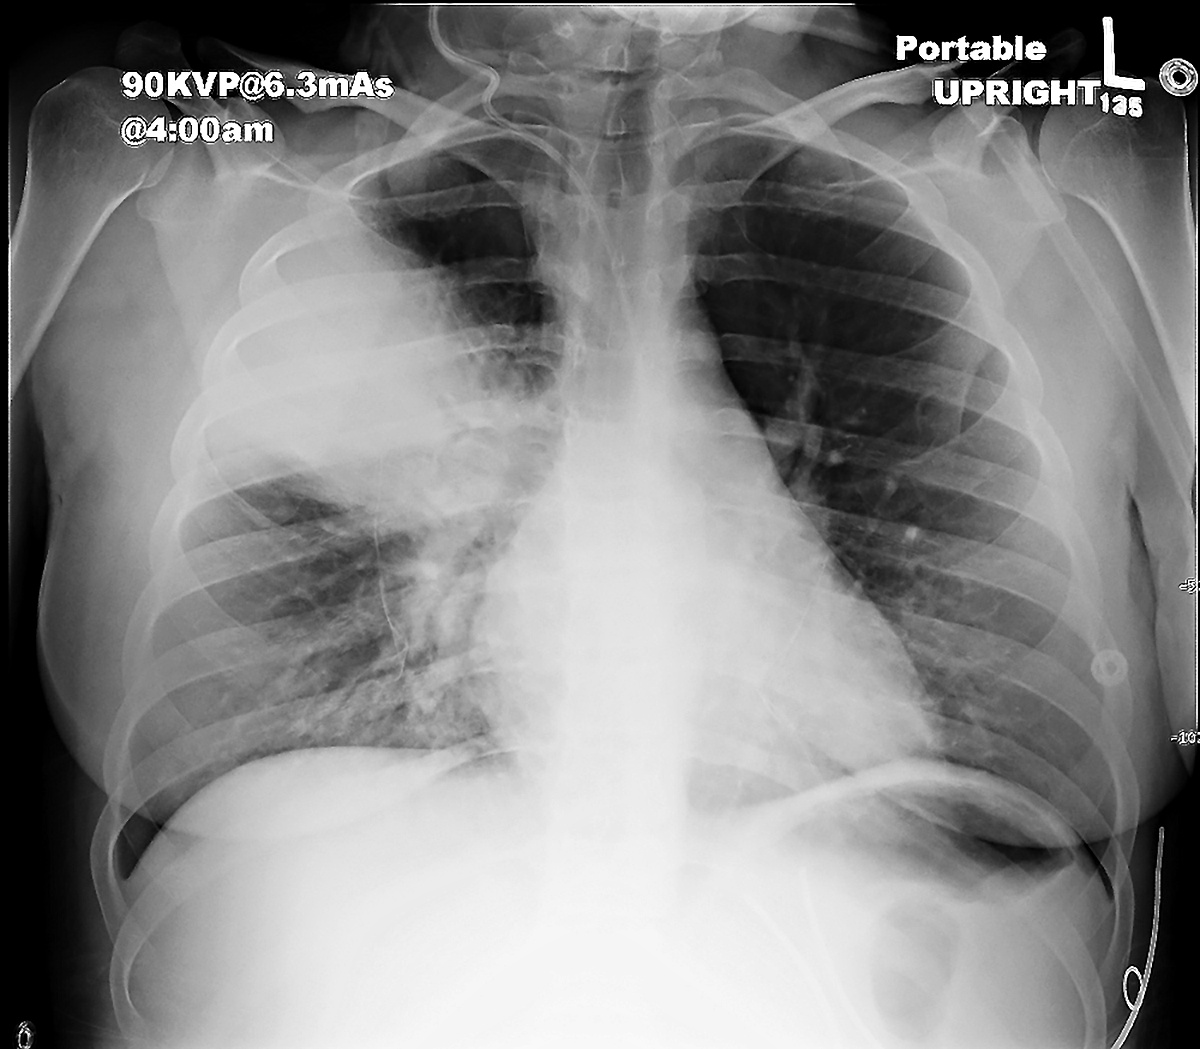

basic case of lines and tubes